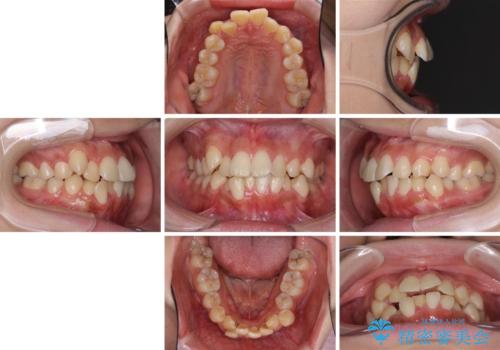

- 八重歯やデコボコをインビザラインで治療したいとのことで来院された患者様です。

インビザライン単体で治療を行うには叢生が強いと判断されたため、事前にワイヤー装置で抜歯矯正を行い、ある程度改善してからインビザラインにて仕上げていくこととしました。